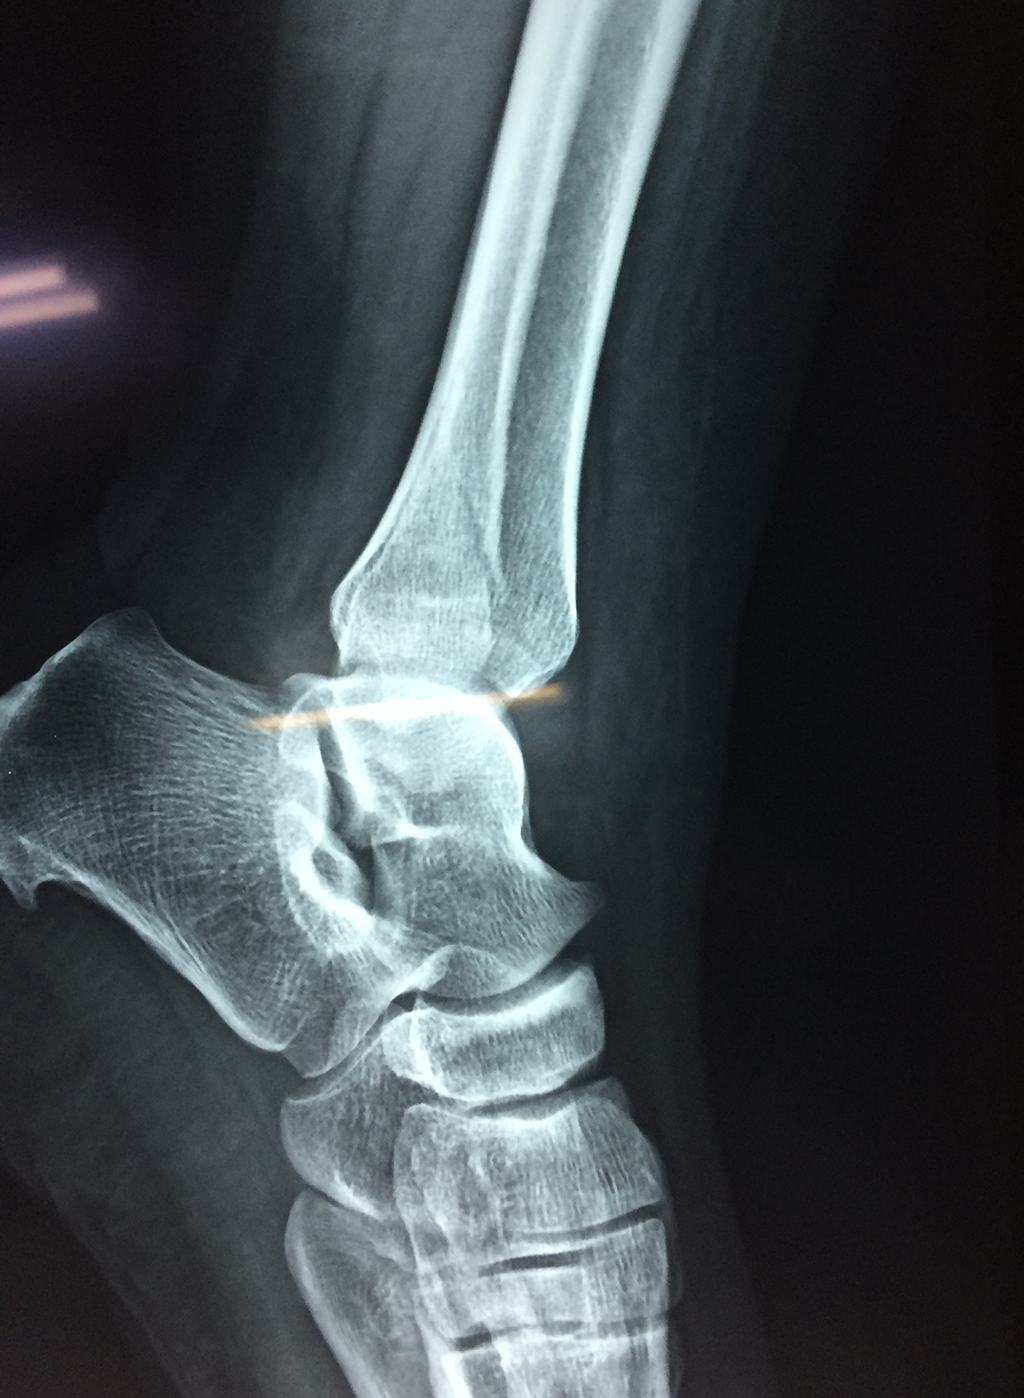

Una fractura de tobillo es la rotura de uno o más de los huesos del tobillo. Estas fracturas pueden ser:

- La fractura se extiende hasta la articulación del tobillo (fractura intra-articular).

Cuando se necesita cirugía, es probable que esta implique el uso de clavijas de metal, tornillos o placas para sostener los huesos en su lugar mientras la fractura se consolida. Los elementos de soporte pueden ser temporales o permanentes.